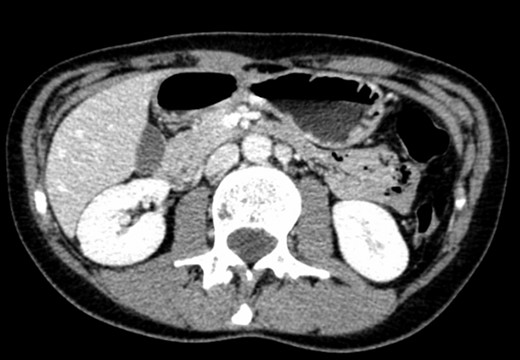

A 39-year-old Caucasian female patient presented to a General surgery outpatient clinic with complaints of epigastric pain, nausea, vomiting and weight loss for more than 5 years. The pain was worse after eating and with supine position. Vomiting was usually initiated 3–4 h after meals and consisted of undigested food. She had no significant prior medical history. On examination, the patient was extremely emaciated, with normal vital signs but with a distended abdomen and fullness over the epigastrium. She had already done an upper endoscopy that only showed gastric stasis. Abdominal ultrasound revealed a reduced angle between the AA and SMA (Fig. 1). An upper GI contrast study was requested, which revealed a distended stomach with delayed gastric emptying and lagging of contrast at the third portion of the duodenum (Fig. 2). Abdominal computed tomography (CT) scan was then performed. It demonstrated a severe distension of the stomach and proximal portions of the duodenum with constriction of the third part of the duodenum between the AA and SMA, with a reduced angle (11°) and shortened distance (4–5 mm) between these two arteries (Figs 3 and 4). These findings were suggestive of an aortomesenteric clamp. Hence, based on known findings, the diagnosis of Wilkie’s syndrome was established.

CT scan—axial CT image of obstruction of the third portion of duodenum between AAA and SMA.